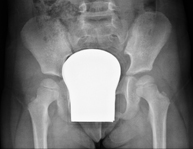

- Pelvis X-ray

This procedure uses X-ray imaging to examine the pelvis, especially the pelvic bones.